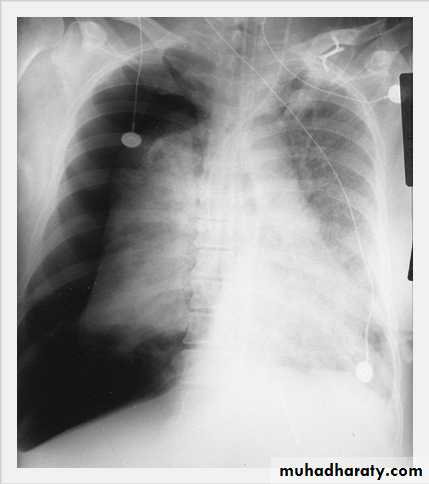

Pleural Effusion on Chest Radiographs.

Posteroanterior (A) and lateral (B) chest radiographs demonstrate the typical meniscoid appearance (arrows) in a patient with a left pleural effusion